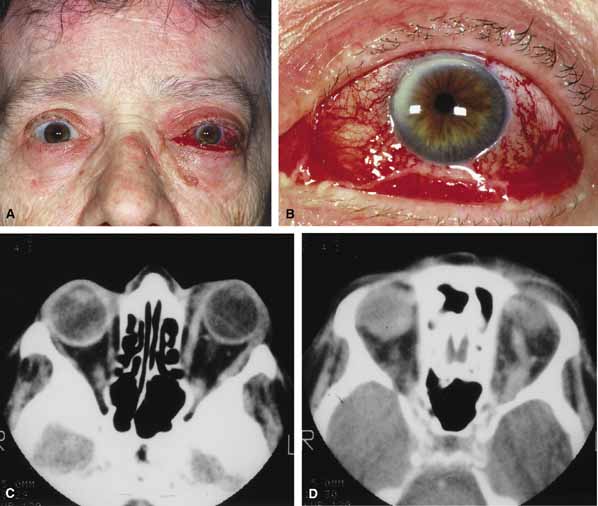

Cartoid cavernous sinus fistula (CCSF) is the most common arteriovenous malformation affecting the orbit and involves abnormal communication between a branch of the carotid artery and the cavernous sinus.79 The resulting high-flow fistula can produce proptosis (may be pulsatile), pain, engorgement of epibulbar veins (corkscrew configurations), limited extraocular motility, raised intraocular pressure and loss of vision (Fig. 12A and 12B). In many cases a bruit may be heard by the patient or examiner. The clinical features may mimic acute thyroid disease, but in contrast to thyroid eye disease, fistulas are usually unilateral. Seventy-five percent of fistulas occur as a result of head trauma; the rest occur spontaneously.79,80 Traumatic causes include head injury (penetrating or nonpenetrating) as well as iatrogenic causes including complications of carotid endarterectomy surgery. The spontaneous fistulas often occur in post-menopausal women. They may be the result of a congenital malformation (e.g., aneurysm or arteriovenous malformation) or associated with atherosclerotic changes, hypertension, collagen vascular disease, or childbirth. Some cases remain idiopathic. The spontaneous fistulas tend to be low-flow shunts in contrast to high-flow traumatic fistulas. Carotid cavernous fistulas can be subdivided as: (1) etiologic (spontaneous or traumatic); (2) hemodynamic (high or low flow), and 3) anatomic (direct or dural).79,80 CT and MRI are useful screening tests and may show dilation of the superior ophthalmic vein, increased extraocular muscle size and enlargement of the cavernous sinus (Fig. 12C and 12D). The definitive diagnostic test is bilateral selective internal and external carotid angiography.

Fig. 12 A. A 68-year-old female developed sudden proptosis (over 2–3 minutes), decreased vision, conjuntival injection, chemosis, and restricted motility. B. Multiple corkscrew vessels are seen secondary to engorgement of the epibulbar vessels. C. Axial computed tomography (CT) scan revealed proptosis and enlargement of the extraocular muscles. D. Axial computed tomography (CT) scan also revealed an enlarged superior ophthalmic vein.